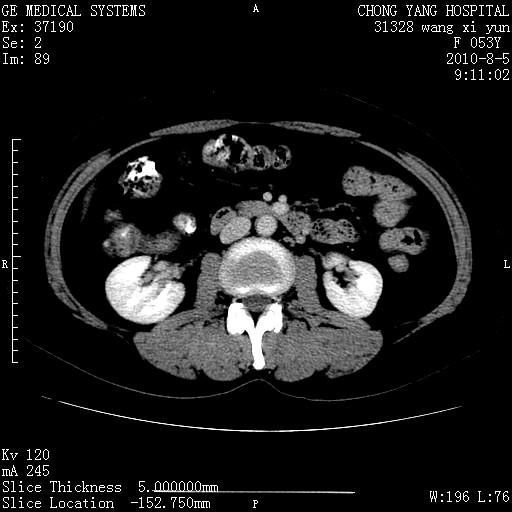

标题: CT28214:F41Y 血尿二十天,建议盆腔平扫加增强。

1)考虑肝左叶胆管细胞癌。2)脂肪肝。